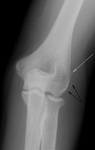

Женщина средних лет. В анамнезе, раньше, травма. Беспокоят боли в локте. Ваше мнение? ![]()

Отрыв коркового слоя боковой поверхности наружного надмыщелка плечевой кости.

Травма. раньше. все то, что мы видим - последствия. как по мне. Не есть ли это признаки эпикондилита?

Светлая стрелочка, то, вполне мочжет быть откал фрагмента "кортикалочки", а, вот черные стрелочки, то мягких тканях. ЧТО?

И мал - мал остеопороз в области соответствующего мышелка и надмыщелка, на мой взгляд, имеет место быть.

Стрелочка указывает на т.н. "шпору" . что является характекрным для эпикондилита - оссификат у места прикрепления мышцы, насколько я понимаю.